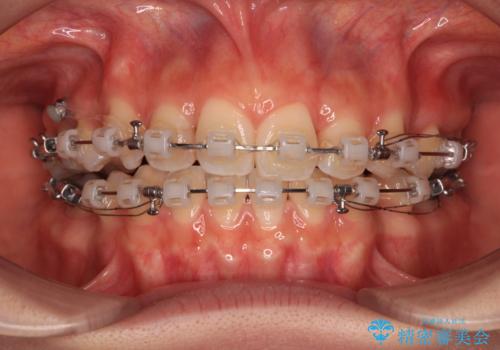

- 矯正装置

- クリアブラケット

- 前歯のデコボコと口元の突出感を気にして来院された患者様です。

口元の突出感が認められ、更には左右で異なる咬合状態であったため、下顎右側は第二小臼歯を、左側は第一小臼歯を抜去することでバランスを取るような治療計画としました。

下顎の抜歯位置を左右で変えることで、最終的に上下正中をほぼ一致させることができました。